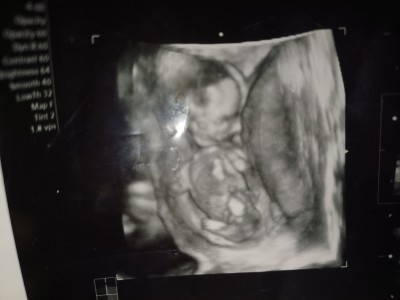

Kızlar sizce ne cinsiyeti doktor tahminim var ama söylemek için erken

image

dedi haftaya gideceğim ama merak ediyorum

12+3  haftaliktim canm gittiğimde